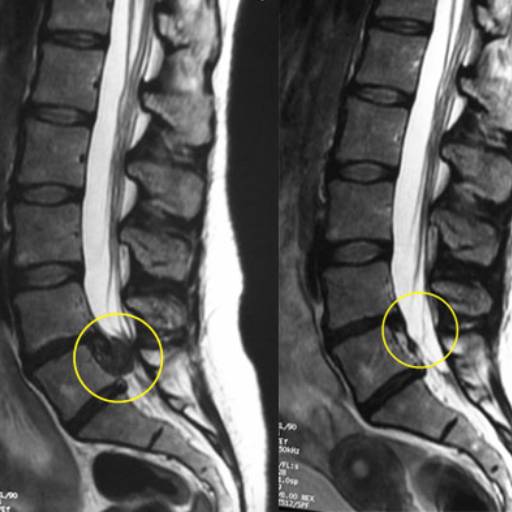

Avaliação, diagnóstico disfuncional e tratamento de discopatias degenerativas, protusões e hérnias de disco, através de técnicas de terapias manuais e exercícios corretivos.